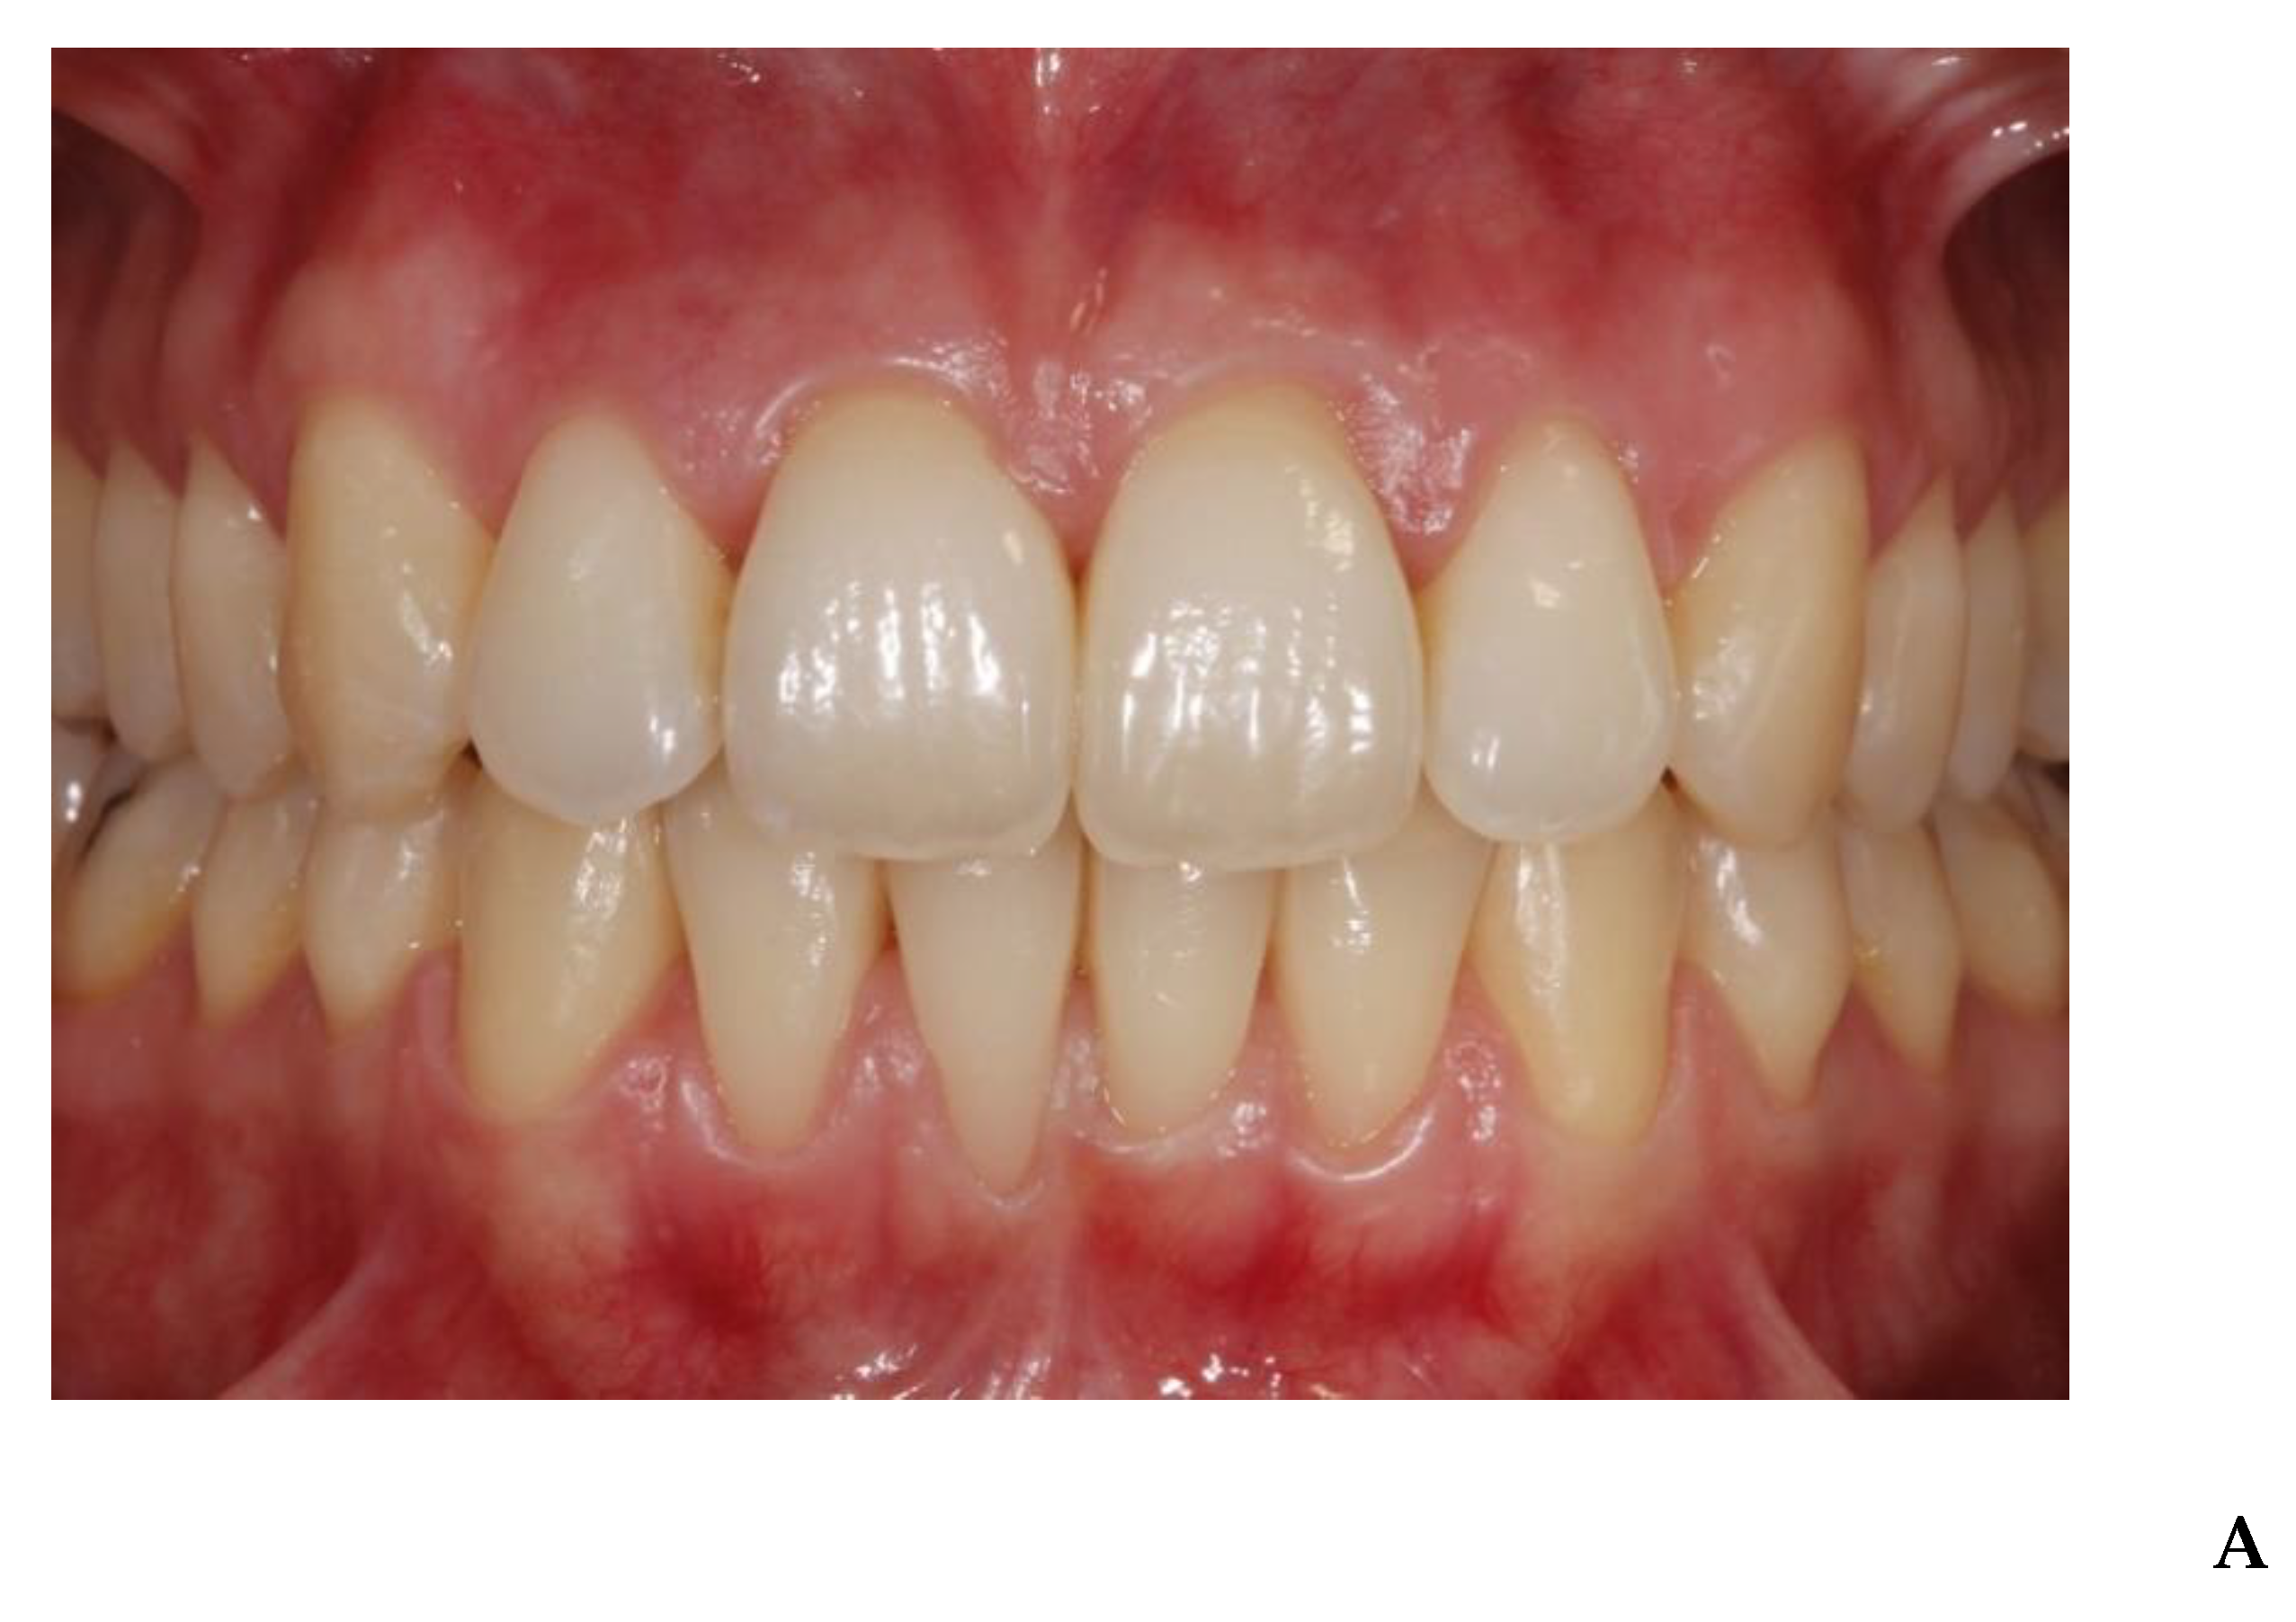

3. Results